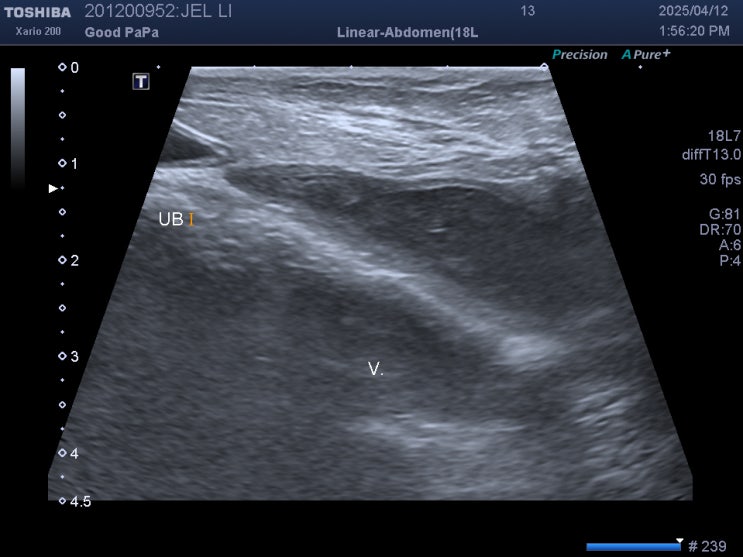

14살 푸들 강아지 질 분비물이 나오는 이유 / 반려견 질 주변 염증 원인 / 중성화한 암컷 강아지가 질에서 고름이 나오는 이유 / 노령견 질염 치료 방법, 비용, 가격

안녕하세요~ 굿파파 수의사입니다. 비가 아침부터 계속 내리는 하루네요~ 따뜻한 커피 한 잔과 함께 행복한...